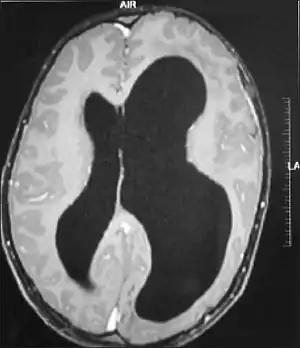

Hemimegalencephaly

Hemimegalencephaly (HME), or unilateral megalencephaly, is a rare congenital disorder affecting all or a part of a cerebral hemisphere.[2] It causes severe seizures, which are often frequent and hard to control. A minority might have seizure control with medicines, but most will need removal or disconnection of the affected hemisphere as the best chance. Uncontrolled, they often cause progressive intellectual disability and brain damage and stop development.[3]

It should be suspected in infants or children with intractable, frequent seizures.[4] On a CT scan, the affected part is distorted and enlarged.[9] It can be diagnosed prenatally, but a lot of cases go undiagnosed until seizures begin. Ultrasound can display asymmetrical brain hemispheres.[5]